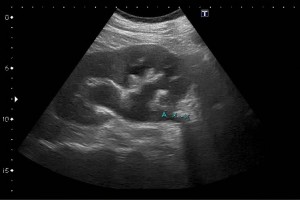

Diplomados en Ultrasonografía